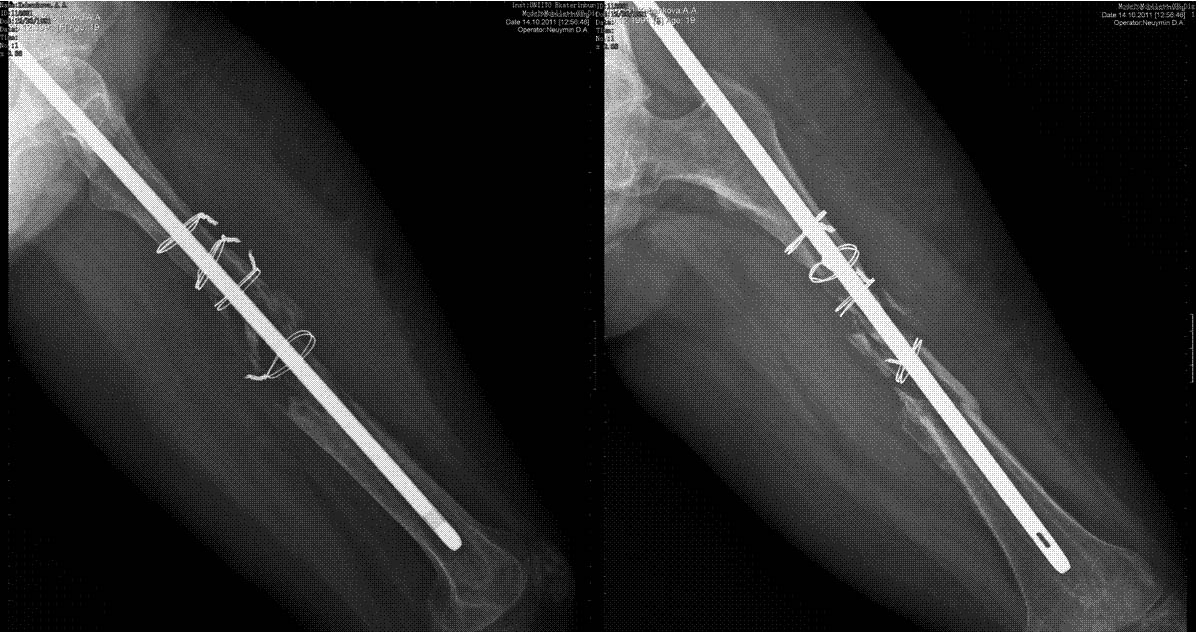

дефект бедренной кости при интрамедуллярном остеосинтезе

Уважаемые коллеги, выскажите пожалуйста свое мнение.пациентка 19 лет. выполнен остеосинтез стержнем,

в послеоперационном периоде лизирование кости между проволочными петлями. у пациентки укорочение бедра 3,4см.+ дефект 10см.

Да и укорочение выглядит куда больше чем 3-4 см

Уважаемый Александр, конечно очень мало информации, но исходя из снимков, лизис кости возможно связан с фиброзной дисплазией или опухолью,если конечно вы исключили инфекцию, хотя на снимках не видно воспаления мягких тканей.

Гипотрофический ложный сустав (возможно инфицированный) и нестабильность имплантата. Он мигрирует кверху.

предоперационные снимки и сразу после синтеза очень плохого качества, но дефекта между серкляжами нет. не считая серкляжей репозиция выполнена удовлетворительно. воспалительных явлений в послеоперационном периоде не было, пациентка ходит на костылях не нагружая конечность. ортопедическое укорочение действительно 3 см., выстояние стержня из точки входа сразу после операции выявлено.

интересно было бы услышать мнения о возможных причинах лизиса, склоняемся к версии о сдавлении серкляжными петлями, что на фоне отсутствия нагрузки дало отрицательный результат.